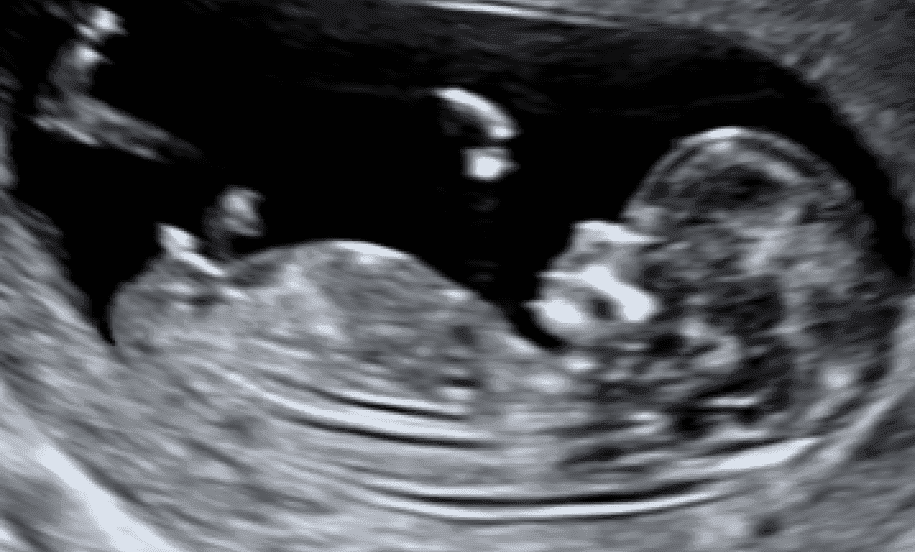

Dating Scan

- Confirm a single/multiple pregnancy of an early/viable pregnancy

- Determine fetal gestation age.

- Between 8 and 14 weeks.

- Crown Rump Length (CRL) measurement.

- Confirmation of heartbeat

- 2x b/w images.

- 30 minutes appointment.